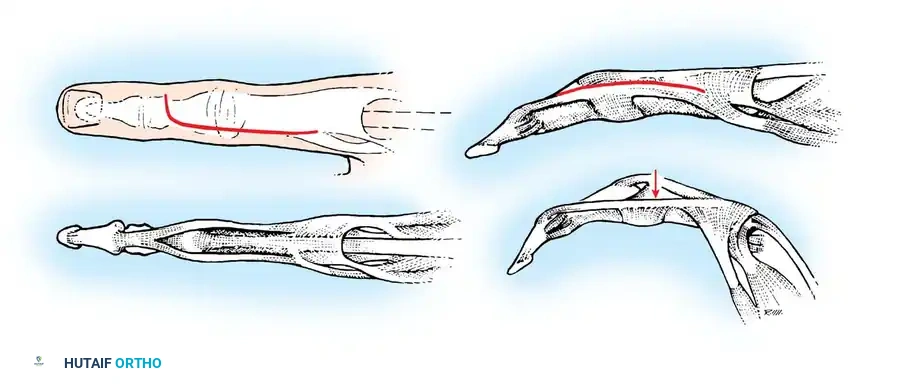

The Bunnell Test for Intrinsic Tightness:

To perform this test, the MCP joint is passively held in maximum extension. This maneuver places the intrinsic muscles on stretch. If the intrinsics are tight, passive flexion of the PIP joint is prevented or significantly limited. Conversely, when the MCP joint is passively flexed (relaxing the intrinsics), passive flexion of the PIP joint increases.

Fig. 70-11 The Bunnell test for intrinsic tightness. Extension of the MCP joint exacerbates PIP extension forces if the intrinsics are contracted.

Surgical Warning: With ulnar drift of the fingers, intrinsic tightness may be present only on the ulnar side. To test this accurately, axial alignment of the finger with the metacarpal must be maintained. Any ulnar deviation at the MCP joint during the test slackens the intrinsics on the ulnar side and will yield a false-negative result.